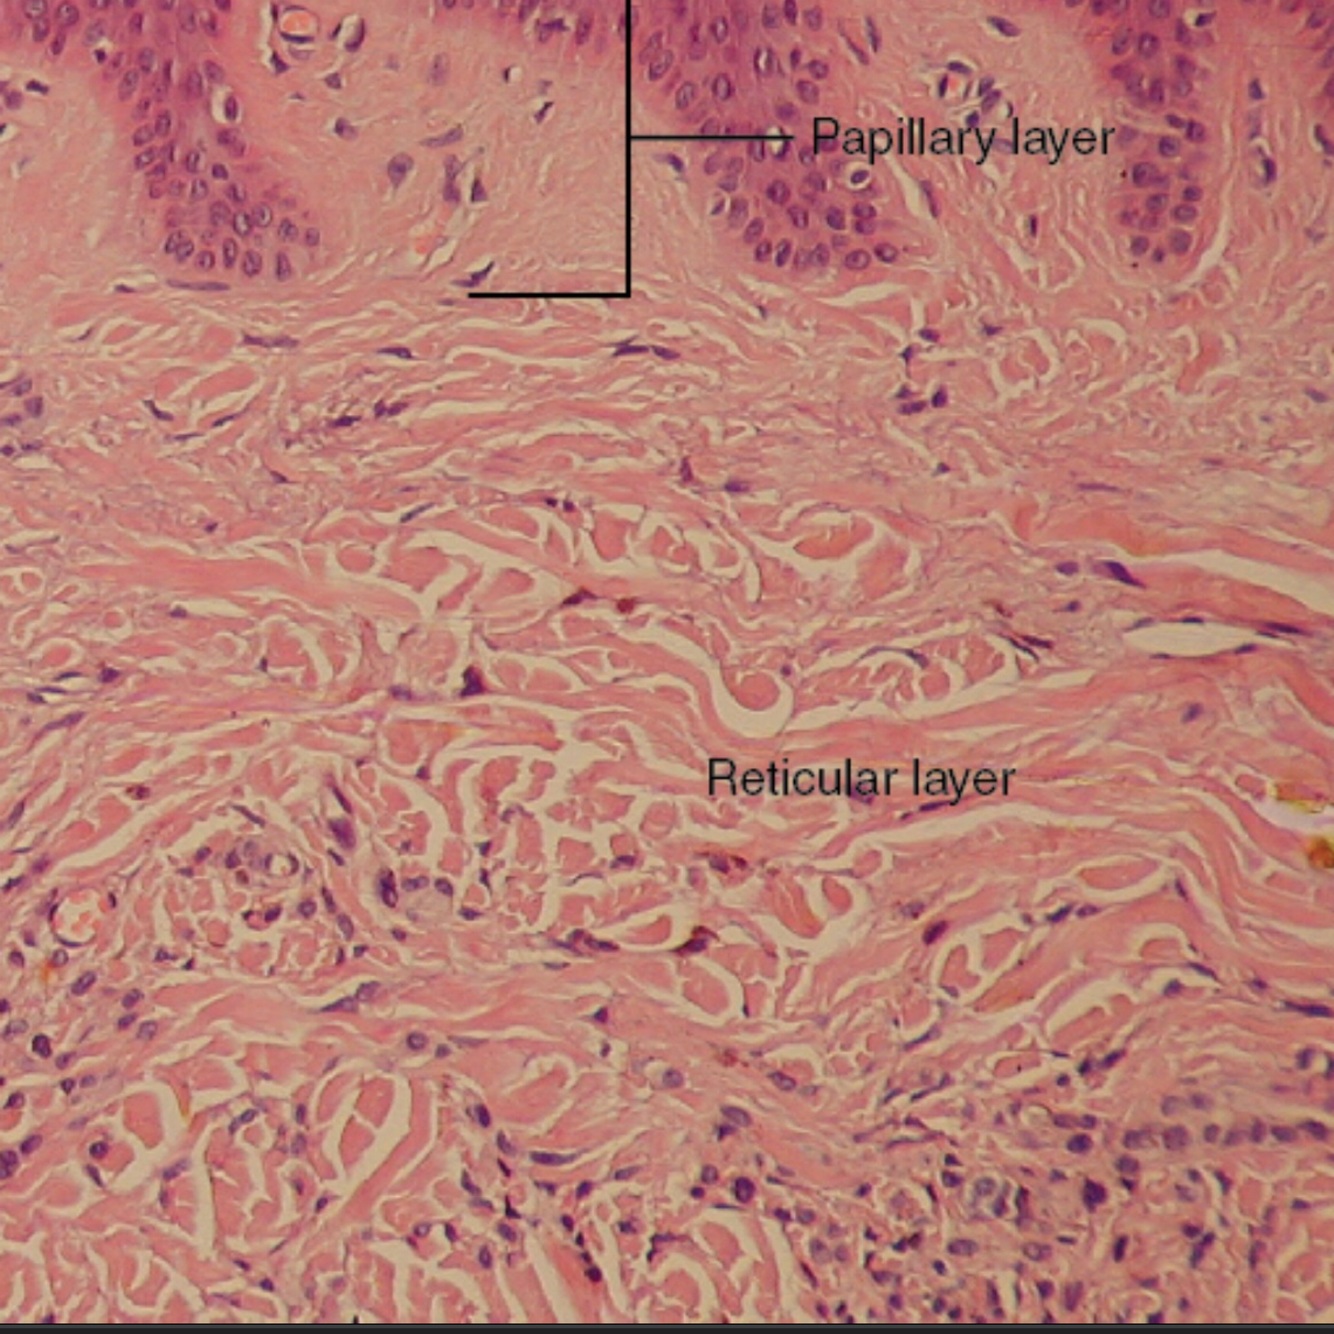

Papillary layer

Upper 1/3 of the dermis

*is areolar connective tissue

Reticular Layer

Lower 2/3 of the dermis

*is dense irregular tissue